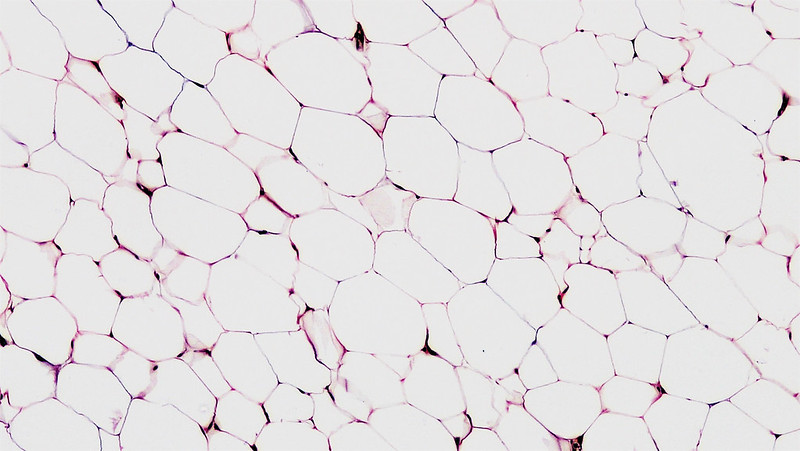

Univakouläre Adipozyten im weißen Fettgewebe:

- Histologische Merkmale:

- Im histologischen Schnitt wirkt die Zelle leer, da das Fett bei der Standardpräparation herausgelöst wird

- Zytoplasma

bleibt als schmaler Saum sichtbar, der Zellkern ist randständig abgeplattet (Siegelringform) - Nachweis mit Fettfärbungen an Gefrierschnitten

- Univakuoläre Adipozyten enthalten jeweils einen großen Fetttropfen, der Zellkern und Zytoplasma

an den Rand drängt - Lipidtropfen besitzen eine Phospholipid-Monoschicht (keine Doppelschicht) mit assoziierten Proteinen (v. a. Perilipin).